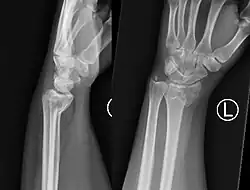

A Smith's fracture, is a fracture of the distal radius.[1]

The distal fracture fragment is displaced volarly (ventrally), as opposed to a Colles' fracture which the fragment is displaced dorsally. Depending on the severity of the impact, there may be one or many fragments and it may or may not involve the articular surface of the wrist joint.

Two views should be obtained: AP and lateral.

PA radiography will look very similar to a Colles' fracture, with a fracture along the distal metaphysis of the radius (can be shortened or comminuted). Lateral radiography will demonstrate volar angulation / displacement of the fracture.[6]